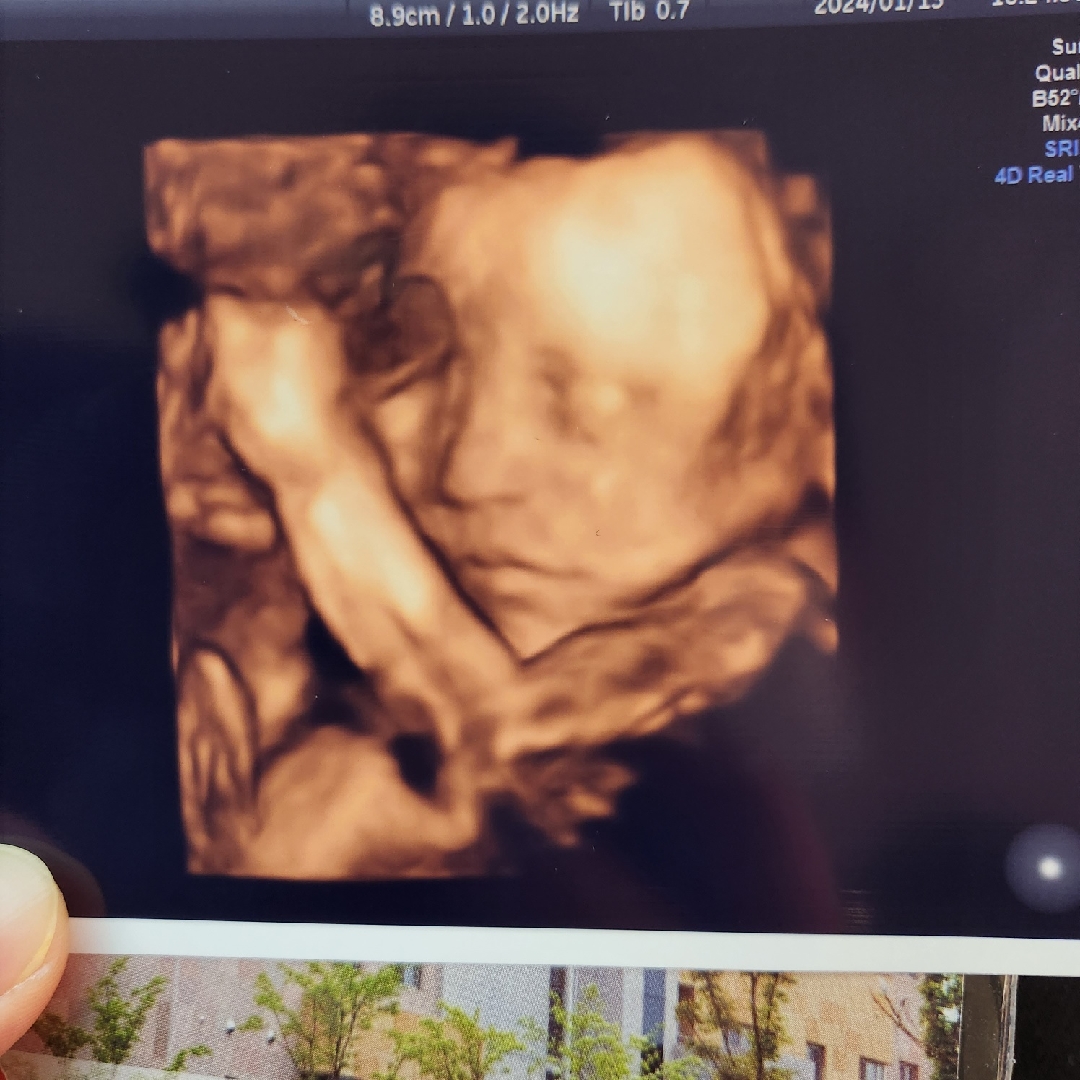

처음 확인한 우리 아가 얼굴

25주차 산모에요 ㅎㅎ 항상 벽쪽에 얼굴을 숨기고 있어서 귀만 보였었는데 입체초음파 보기 전에 태명 열심히 부르고 걷기 했더니 이렇게 얼굴을 잘 보여줬네요 ㅎㅎ 신기하게도 저희 엄마와 여동생을 닮은 듯한 코♡ 아직도 제 뱃속에 아기가 있다는게 실감이 안납니다! 이날 임당확정도 받아서 식단 관리하는 중이지만 ㅠㅠ